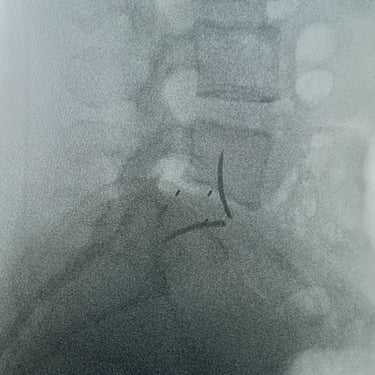

La cirugía ALIF (Anterior Lumbar Interbody Fusion), o Fusión Lumbar Intercorporal Anterior, es una técnica quirúrgica utilizada para tratar patologías de la columna lumbar como la degeneración discal, la inestabilidad vertebral o las hernias lumbares recurrentes. Mediante un abordaje anterior, se extrae el disco dañado y se coloca un injerto o caja intersomática que permite lograr la fusión estable entre las vértebras. Este procedimiento favorece una mejor restauración del espacio discal, alineación lumbar y preservación muscular. La cirugía ALIF es realizada por un equipo especializado en neurocirugía de columna, garantizando precisión y resultados funcionales óptimos.